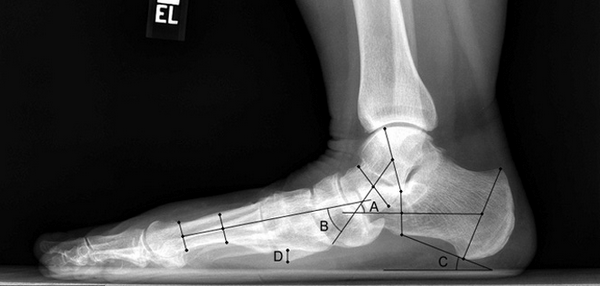

Рентген плоской стопы.

Медиализирующая остеотомия пяточной кости в сочетании с таранно-ладъевидным артродезом.